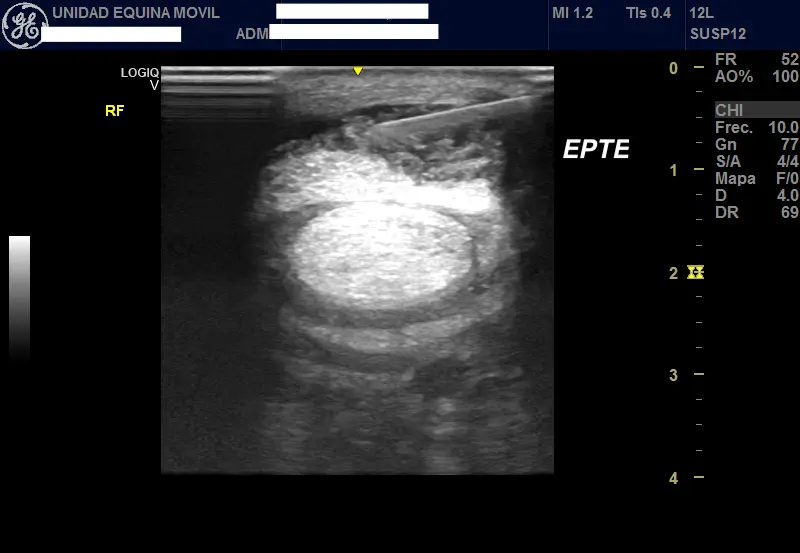

Advanced Diagnostic Imaging

We carry out diagnostic tests such as scintigraphy, magnetic resonance imaging, among others, in collaboration with equine veterinary hospitals.